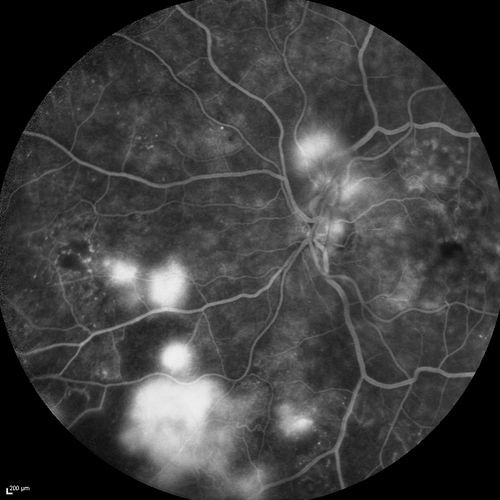

FA showing NVE, NVD, non- perfusion left eye inferonasally with neovascularization at the margin of the non-perfusion

Proliferative Diabetic Retinopathy - Lacy Neovascularization of the Disc - Photo of Fresh Panretinal (Scatter) Photocoagulation